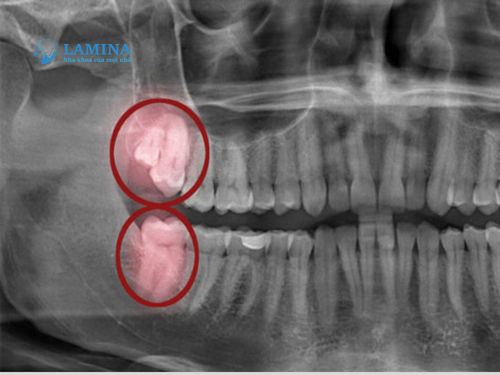

– Kiểm tra và chụp phim X-quang: Bác sĩ sẽ chụp X-quang để xem có sót chân răng, mảnh xương hay tổn thương dây thần kinh không. Đây là bước quan trọng để xác định nguyên nhân chính xác.

4. Ảnh hưởng dây thần kinh

Răng khôn mọc lệch gần dây thần kinh hàm dưới, khi nhổ có thể gây tổn thương hoặc chèn ép nhẹ dây thần kinh, khiến người bệnh cảm giác đau tê kéo dài vùng môi hoặc cằm.